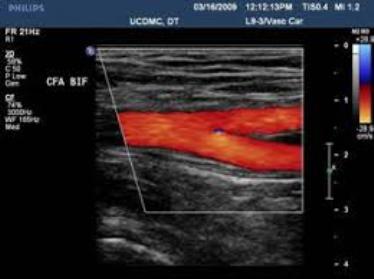

At Ultracare Diagnostic, we understand the importance of your health and the essentiality of accurate diagnosis. Therefore, we offer you comprehensive care and a non-invasive Ultrasound test that helps determine how well your body organs are functioning and if there are any abnormalities present. This helps the doctor to provide you with an accurate diagnosis and treatment for the same

We offers Best Services With Experienced hand on Sonology